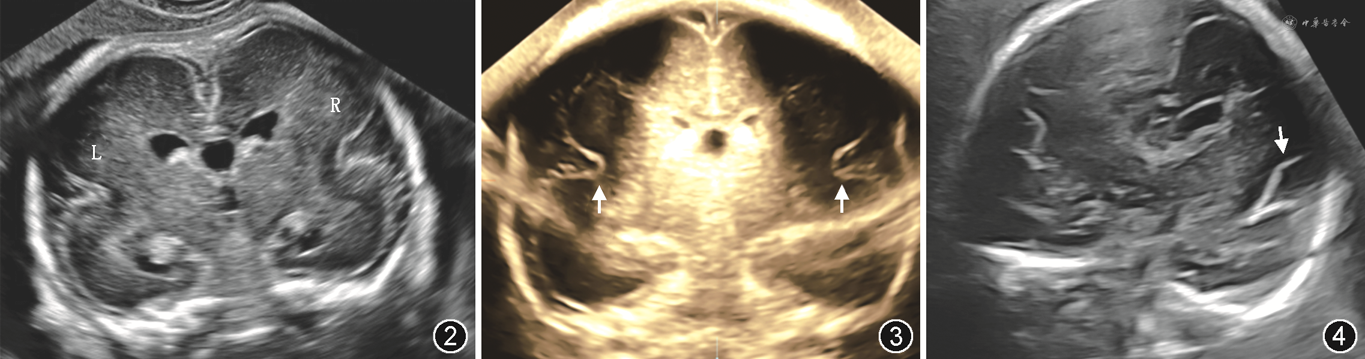

1.超声检查:12例因致病性或可疑致病性基因结果最终诊断为MCD胎儿中,10例双侧大脑外侧裂形态异常且对称,其中6例外侧裂宽大表浅、4例异常成角,另2例双侧形态异常,且形态不对称,均为一侧宽大表浅,另一侧异常成角。大脑外侧裂形态异常胎儿典型NSG检查图像见图2~4。

注:L:左侧;R:右侧;NGS:神经学超声(neurosonogram)